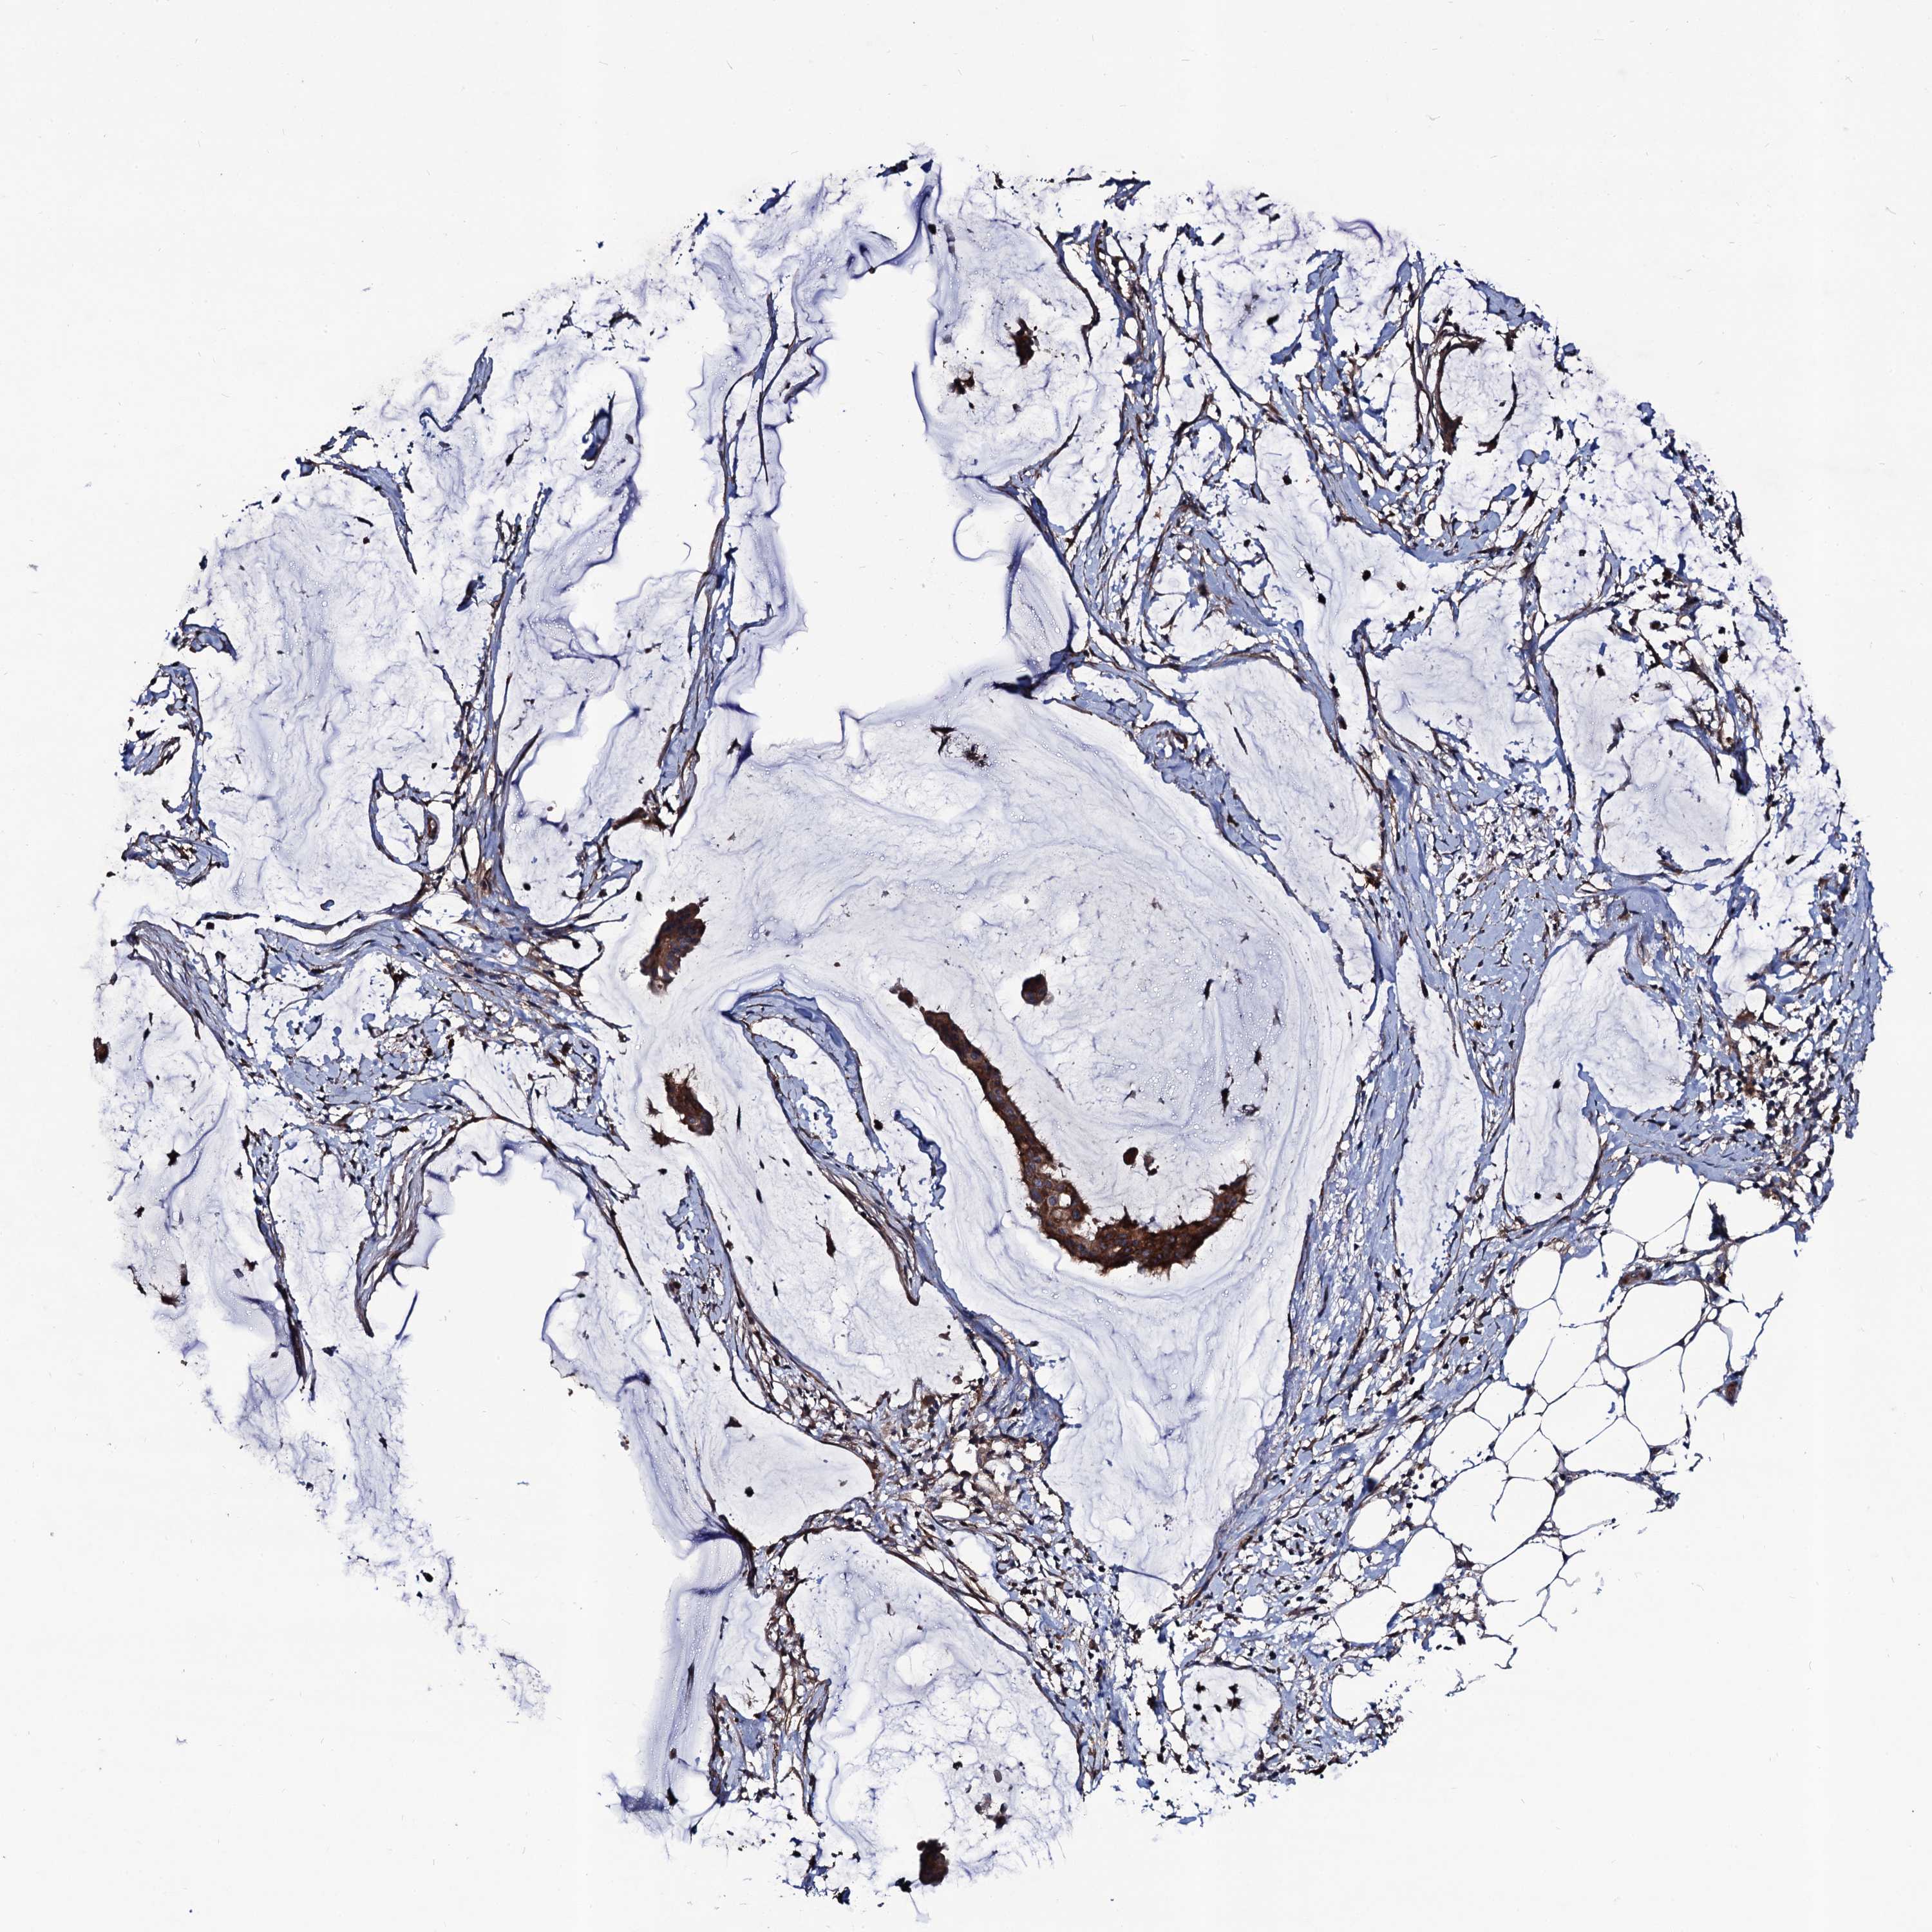

OVARIAN CANCER - Protein expressioni

A mouse-over function shows sample information and annotation data. Click on an image to view it in a full screen mode. Samples can be filtered based on level of antibody staining by selecting one or several of the following categories: high, medium, low and not detected. The assay and annotation is described here.

Note that samples used for immunohistochemistry by the Human Protein Atlas do not correspond to samples in the TCGA dataset.

Antibody stainingi

Antibody staining in the annotated cell types in the current human tissue is reported as not detected, low, medium, or high, based on conventional immunohistochemistry profiling in selected tissues. This score is based on the combination of the staining intensity and fraction of stained cells.

Each image is clickable and will lead to virtual microscopy that enables deeper exploration of all samples and also displays staining intensity scores, fraction scores and subcellular localization as well as patient and tissue information for each sample.

Antibody HPA041507

Antibody HPA041599

Cystadenocarcinoma, serous, NOS

Carcinoma, endometroid

Cystadenocarcinoma, mucinous, NOS

Carcinoma, NOS